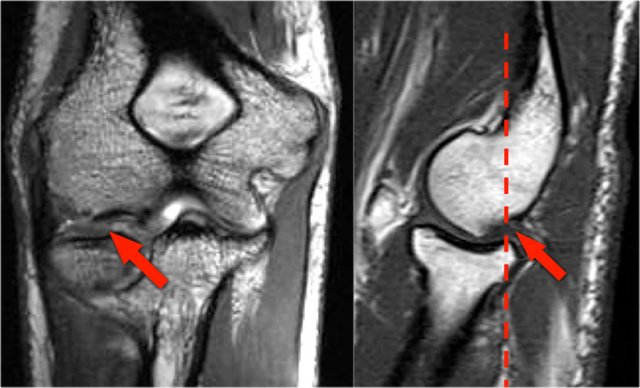

Due to the valgus overload there are shear forces on the posteromedial part of the humeroulnar joint.

Notice the subchondral sclerosis seen on the T1W-image (red arrow).

On the T2W-image there is subchondral bone marrow edema and cartilage loss (yellow arrow).

These are images of a 20 year old baseball pitcher.

On the coronal images there is a beautiful anterior bundle of the UCL, but notice that there is osteophyte formation on the medial part of the joint (red arrow).

As we go further posteriorly there is a small area of low signal intensity (yellow arrow), which is an avulsion of part of the UCL.